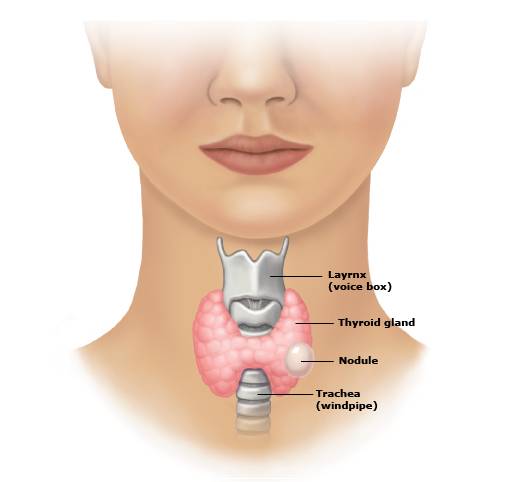

Thyroid Cancer

Thyroid cancer occurs in the cells of the thyroid — a butterfly-shaped gland located at the base of your neck, just below your Adam's a...